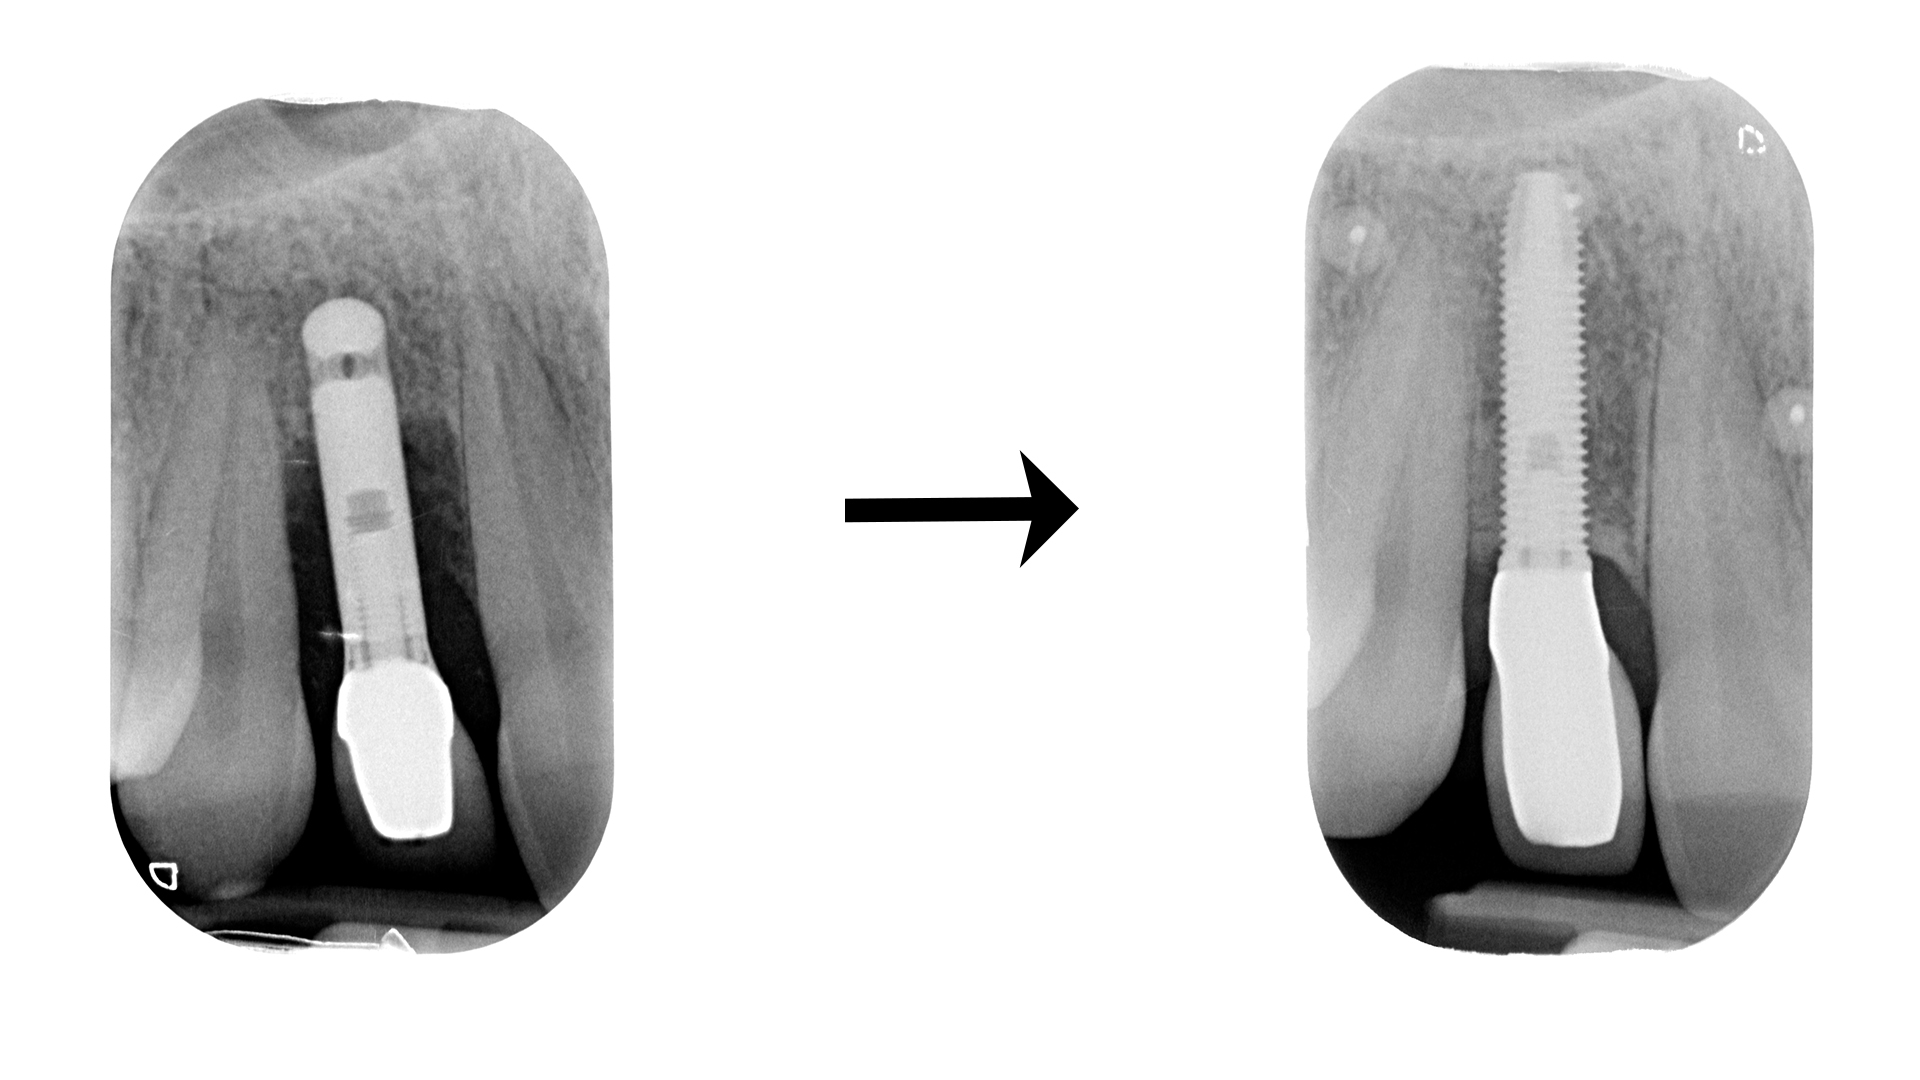

Casi rognosi come questo:

O questo:

O questo: